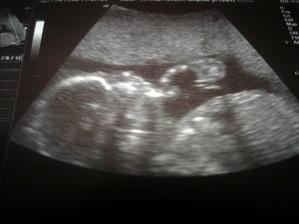

3.11. velký utz, dopadl na 1, dle utz jsme 12+5, ale dle ovu spíš 12+2 🙂, šíjové projasnění 1,2. Mimi měří od hlavičky ke kostrči už 7cm. Pořád se vrtělo....asi se mu to moc nelíbilo :(. Zážitek to byl nádherný a jsem ráda, že si ho mohl zažít i manža...byl nadšený.... 🙂